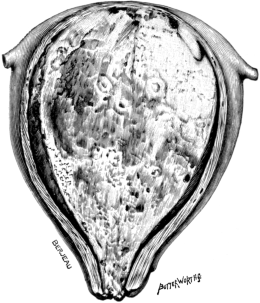

| 1. | Secondary Cancer of the Ovary | 15 |

| 2. | Secondary Cancer of the Ovary in Section | 15 |